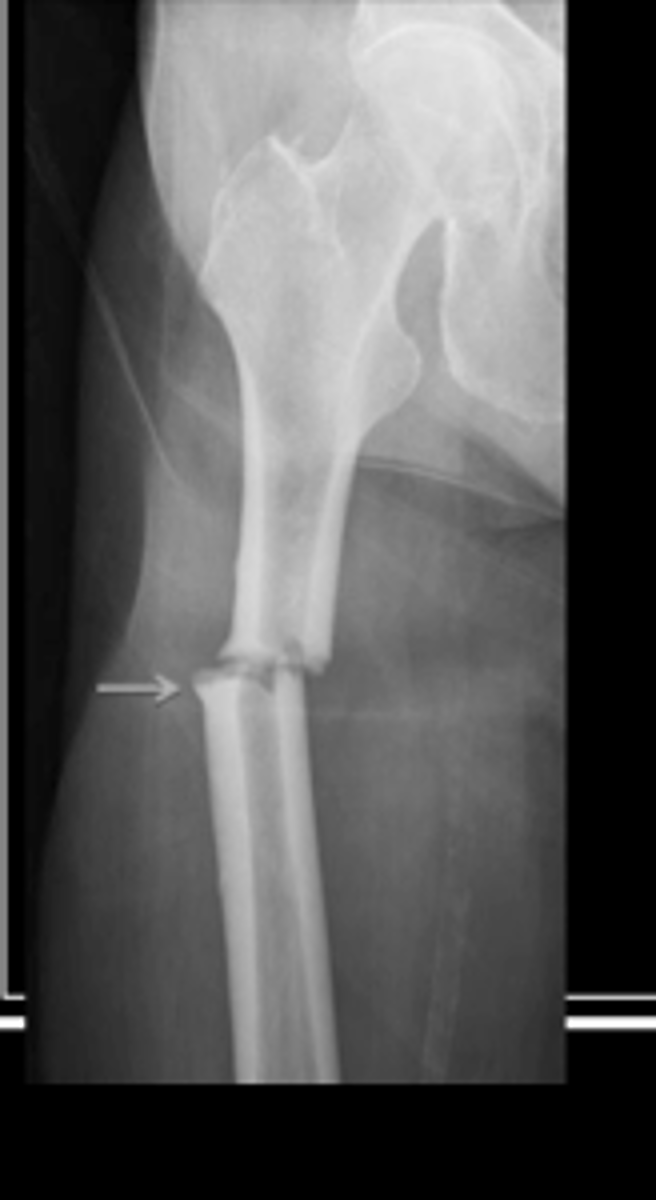

Oblique fracture

fracture at an angle to the bone